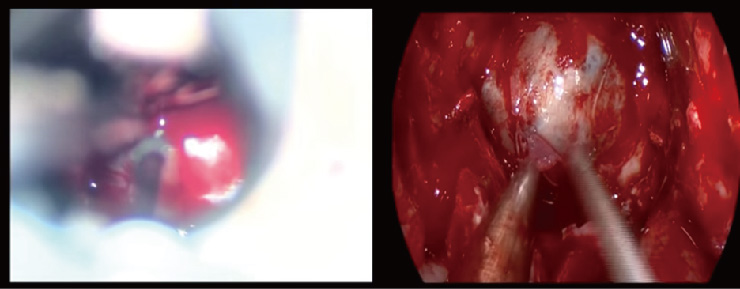

| (A) 腦下垂體腫瘤壓迫到視神經, 術前核磁共振檢查。(B) 經鼻內視鏡腦下垂體腫瘤切除術後腫瘤完全切除且視神經壓迫獲得緩解 |

由於手術器械與內視鏡系統的進步,「經鼻內視鏡手術移除腦下垂體腫瘤」是目前世界上治療腦垂體腫瘤共通的趨勢,除了有不需剃頭髮、不需開顱手術的優點之外,對神經外科醫師而言能有更良好的視野與操作空間,故可以避免一些傳統顯微鏡手術容易有的病發症,對病人是多一層保障,也是目前治療腦下垂體腫瘤的首選。

病人在麻醉以後,神經外科醫師會將內視鏡從鼻孔置入病患鼻腔,經由蝶竇到腦下垂體附近,進行腫瘤切除。目前大部份醫學中心的神經外科醫生皆有成熟的技術以及經驗可以利用經鼻內視鏡經蝶竇手術安全的切除大部份的良性腦下垂體腫瘤。不光是本文的主題良性腦下垂體腫瘤,適合接受經鼻內視鏡手術之腦下垂體疾病包括: Rathke氏囊腫(Rathke’s cysts)與部分的顱咽瘤(craniopharyngioma)等。

一. 經鼻內視鏡手術的優點:不需在鼻中隔作切割,對鼻腔粘膜的破壞較低,故手術後病患的不適感會較少見。另外內視鏡的優點是解析度較高,故手術中醫師可以看得比較清楚,並可利用30度內視鏡檢查是否腫瘤有完全切除。目前有研究顯示內視鏡手術(較傳統手術)有較高的腫瘤切除率與較低的併發症。